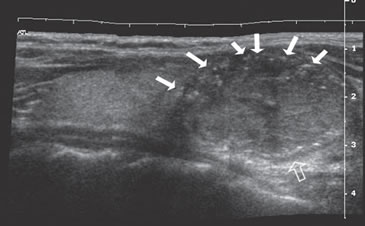

Figura 15. a) Cáncer papilar sólido de bordes lobulados (flechas) que muestra una gruesa calcificación central (flecha abierta) y múltiples

microcalcificaciones; b) Adenopatía cervical del grupo IV del mismo paciente (figura 15 a), hiperecogénica, con elementos quísticos (flecha

blanca) y microcalcificaciones agrupadas (flechas negras), típica de cáncer papilar; c) Adenopatías de grupo IV de un cáncer papilar, de

forma redondeada, hiperecogénicas, con pérdida del hilio, una anterior a la arteria carótida común (flecha) y otra lateral a la vena yugular

interna (flecha abierta); d) Corte sagital de la adenopatía lateral de la imagen 15 c), que en “doppler color” muestra vascularización patológica

y pérdida del hilio.